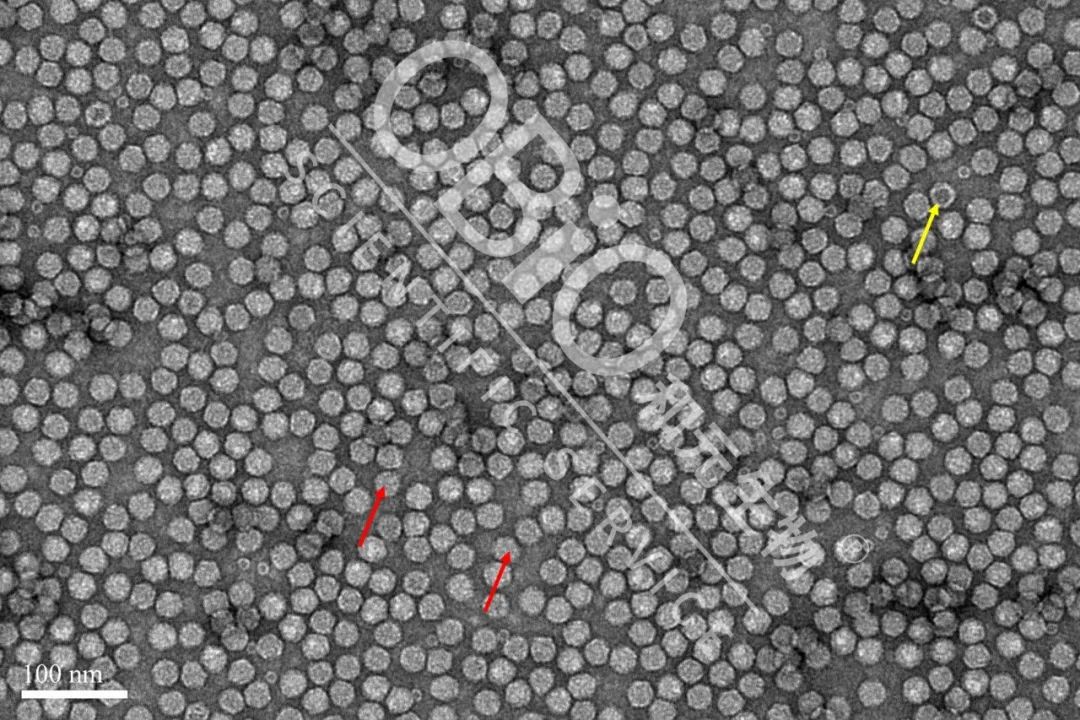

图2 k8凯发(中国)天生赢家·一触即发 rAAV载体生产空壳率

电镜结果:包装DNA基因组的病毒颗粒为实心颗粒(红色箭头);空病毒颗粒中间存在空洞(黄色箭头)